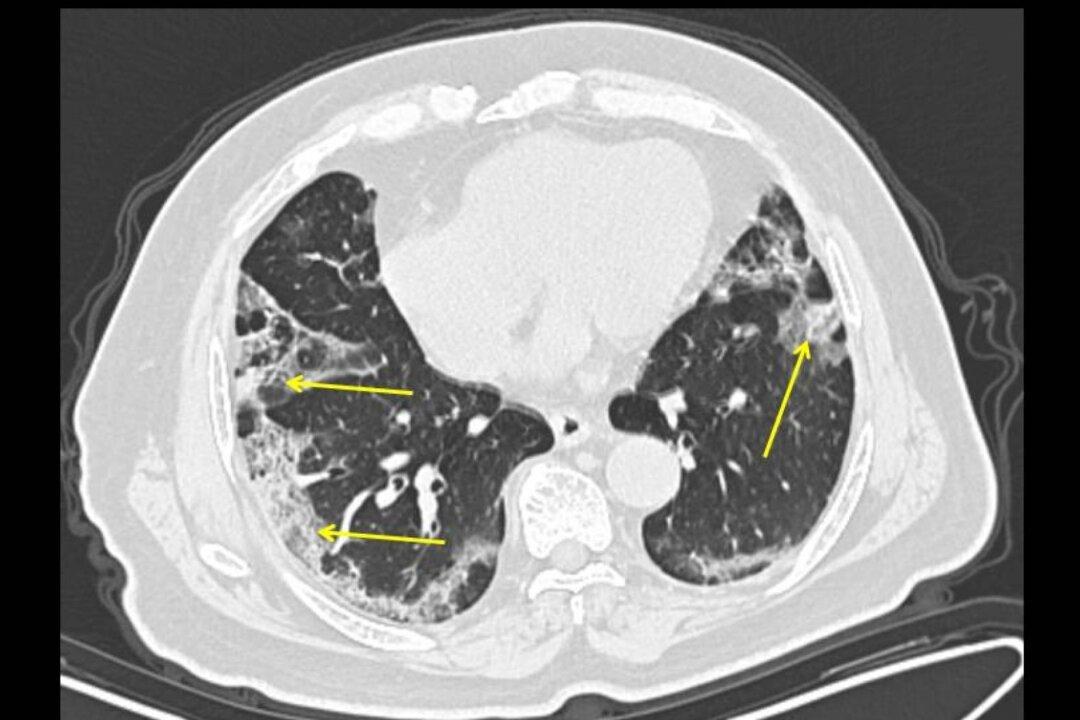

The first U.S. doctors to analyze a COVID-19 coronavirus patients’ lungs said they were able to identify patterns in the lungs as indicators of the disease as it progressed over time.

Doctors at New York City’s Mount Sinai hospital became the first in the nation to use CT scans on patients from China with COVID-19, they said in a statement on Wednesday, publishing their findings in “Radiology.” The new findings could result in a quicker diagnosis in patients who arrive with potential symptoms of the mysterious new virus.